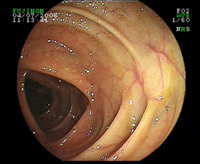

Colon transverse normal